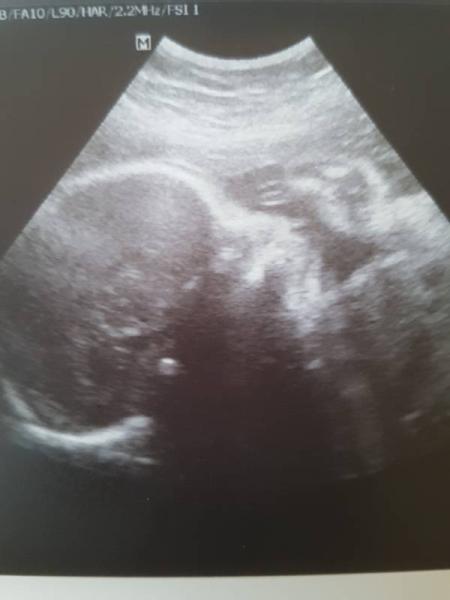

Hallo ihr Lieben ich hoffe es geht euch gut! Mir so bescheiden. Habe heute die letzte große Untersuchung bei 28 +6 gehabt. Alles soweit gut und unauffällig. Die kleine bleibt eine Sie und wiegt ca 1500 g. Sie ist im oberen Bereich in der Grösse. Leider liegt sie noch nicht in Startposition. Der Kopf ist im Bauchnabelbereich und der Popo unten. Aber der Arzt ist zuversichtlich das sie sich noch dreht. Bin mal gespannt ob es noch kommt, mein 2 Sohn hat sich von alleine nicht mehr gedreht und musste von aussen gedreht werden. Ansonsten bleibe ich bis zum Mutterschutz krankgeschrieben. Was nicht verwunderlich ist da es mir immer noch sehr bescheiden geht. Habe aktuell auch noch minus 1 Kg. Aber Hauptsache die kleine holt sich was sie braucht. Ich habe auch schon den Beleg für den Mutterschutz heute erhalten. Liebe Grüße